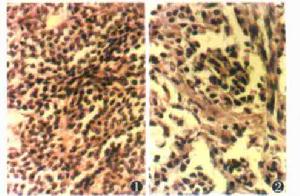

組織病理見擴張的血管腔,內襯單層扁平內皮細胞,內皮細胞周圍為數層或多層血管球細胞。腫瘤內可以有結締組織、平滑肌組織及無髓神經纖維。電鏡下瘤細胞具有平滑肌細胞的特徵,而非外皮細胞。免疫組化對Vimentin及基膜成分染色陽性。